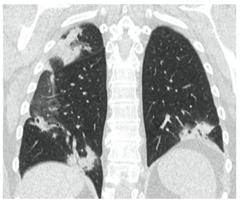

2. Наличие клинических проявлений, указанных в п. 1, в сочетании с характерными изменениями в легких по данным компьютерной томографии (КТ) (см. Приложение 1 настоящих рекомендаций) вне зависимости от результатов однократного лабораторного исследования на наличие РНК SARS-CoV-2 и эпидемиологического анамнеза.

- Изменения при КТ (рентгенографии), типичные для вирусного поражения (объем поражения минимальный или средний; КТ 1-2)

- Изменения в легких при КТ (рентгенографии), типичные для вирусного поражения (объем поражения значительный или субтотальный; КТ 3-4)

- Изменения в легких при КТ (рентгенографии), типичные для вирусного поражения критической степени (объем поражения значительный или субтотальный; КТ 4) или картина ОРДС.

КТ имеет высокую чувствительность в выявлении изменений в легких, характерных для COVID-19. Применение КТ целесообразно для первичной оценки состояния ОГК у пациентов с тяжелыми прогрессирующими формами заболевания, а также для дифференциальной диагностики выявленных изменений и оценки динамики процесса. КТ позволяет выявить характерные изменения в легких у пациентов с COVID-19 еще до появления положительных лабораторных тестов на инфекцию с помощью МАНК. В то же время, КТ выявляет изменения легких у значительного числа пациентов с бессимптомной и легкой формами заболевания, которым не требуется госпитализация. Результаты КТ в этих случаях не влияют на тактику лечения и прогноз заболевания при наличии лабораторного подтверждения COVID-19. Поэтому массовое применение КТ для скрининга асимптомных и легких форм болезни не рекомендуется.